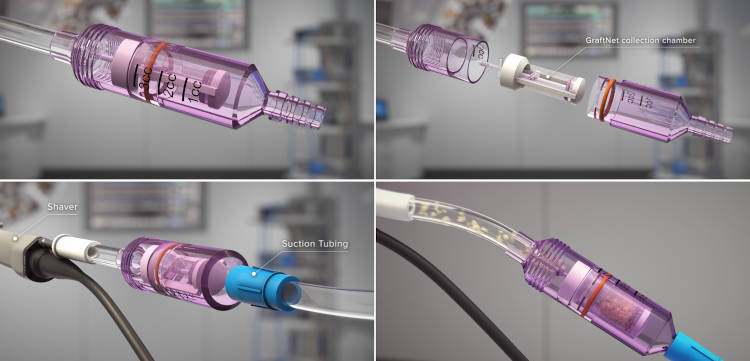

Τον τελευταίο χρόνο, η ομάδα της Β' Ορθοπαιδικής Κλινικής του Ιασώ Θεσσαλίας χρησιμοποιεί την τεχνική Graftnet με εντυπωσιακά αποτελέσματα, όπου στον ίδιο χρόνο συλλέγει υγιή χόνδρο από μη φορτιζόμενη επιφάνεια, τον δυναμοποιεί και ενεργοποιεί ανακατεύοντας τον με αυτόλογους αυξητικούς παράγοντες και τον επανατοποθετεί στη περιοχή της βλάβης όπου θα αναπτυχθεί νέος αρθρικός χόνδρος.